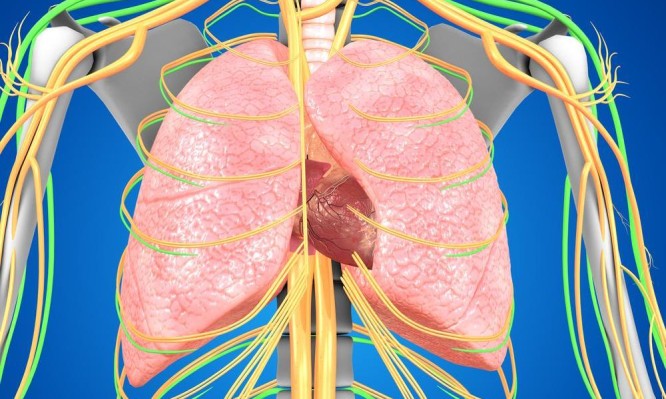

Ύπουλος εχθρός της καρδιάς αποτελεί η πνευμονική υπέρταση η οποία μπορεί να ''φράξει'' τις αρτηρίες της καρδιάς. Τι είναι η...